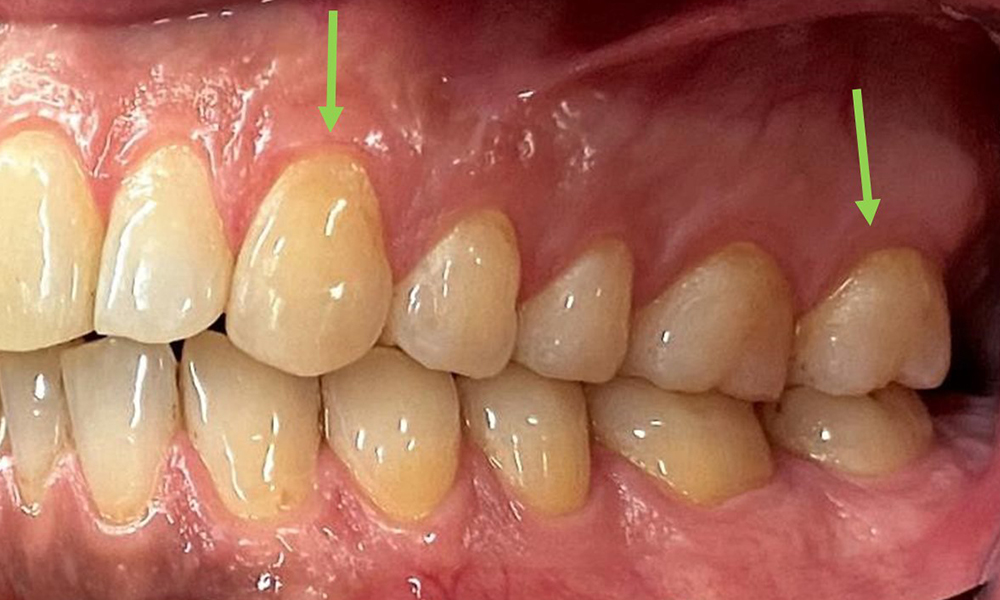

Instruction and motivation are important components of these appointments. Good home-based intraoral hygiene behaviour and understanding are important for patients. Plaque accumulation is particularly evident in the cervical regions (Fig. 8).

The arrows indicate plaque accumulations in the cervical region

Fig. 8: The arrows indicate plaque accumulations in the cervical region, © Dr R. Krapf

These must be discussed with the patient, and improvements to the teeth-brushing technique must be practised. A soft toothbrush attachment is recommended for home-based intraoral hygiene due to the presence of erosions and attritions.